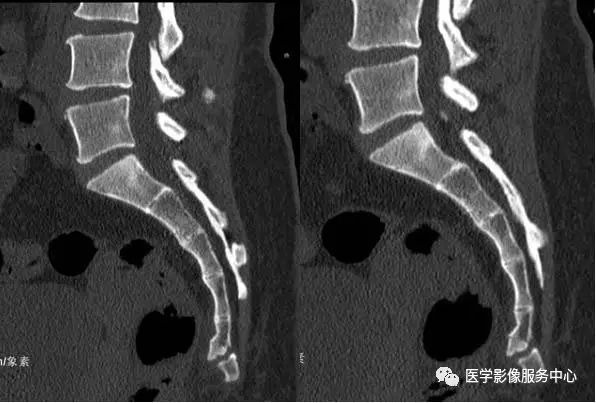

骶骨由5块骶骨融合成一块形成,尾骨由3-5组成。在人类的退化结构中骶尾骨变异较大,特别是侧位的弯曲形态变异较大。研究表明在X线侧位片上骶尾骨共同向前弯曲,但由于其变异较大,弯曲形态各异。

按不同的弯曲形态将其分为:均匀弯曲型、骶骨成角型、尾骨成角型、尾骨脱位型4种类型(见图1-9),其中骶骨成角一般在S3、S4-5和S5部位,成角最大为70°。尾骨成角常在尾1-2或尾2-3部位,成角最大可达80°。

图1:均匀弯曲型;图2:骶骨成角型(骶3);图3:骶骨成角型(骶4-5);图4:骶骨成角型(骶5);图5:尾骨成角型(尾1);图6:尾骨成角型(尾1-2);图7:尾骨成角型(尾2-3);图8:尾骨脱位型;图9:尾骨脱位型